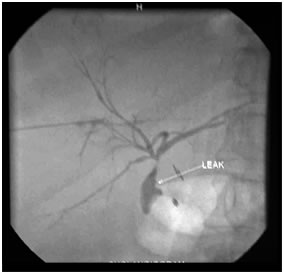

PTBD gram showing biliiary leak